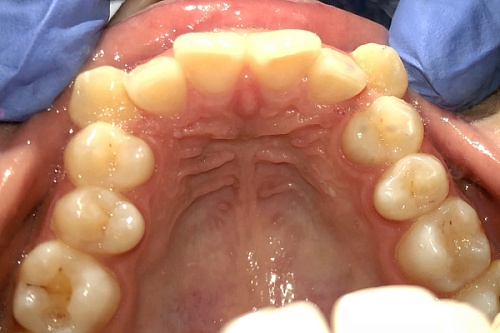

Изменения тканей, которые окружают корни зубов, к сожалению, неизбежны и с возрастом наблюдаются у всех, однако в разном объеме. Так, на развитие пародонтита влияет болезнетворная микрофлора полости рта, которая есть у каждого из нас, но на мы в силах повлиять на ее количество.

Сохранить зубы и пародонт помогает правильная гигиена полости рта дома и в кресле стоматолога, а также своевременное протезирование и имплантация, которые замещают удаленные зубы и равномерно распределяют жевательную нагрузку, не позволяя костной ткани атрофироваться.